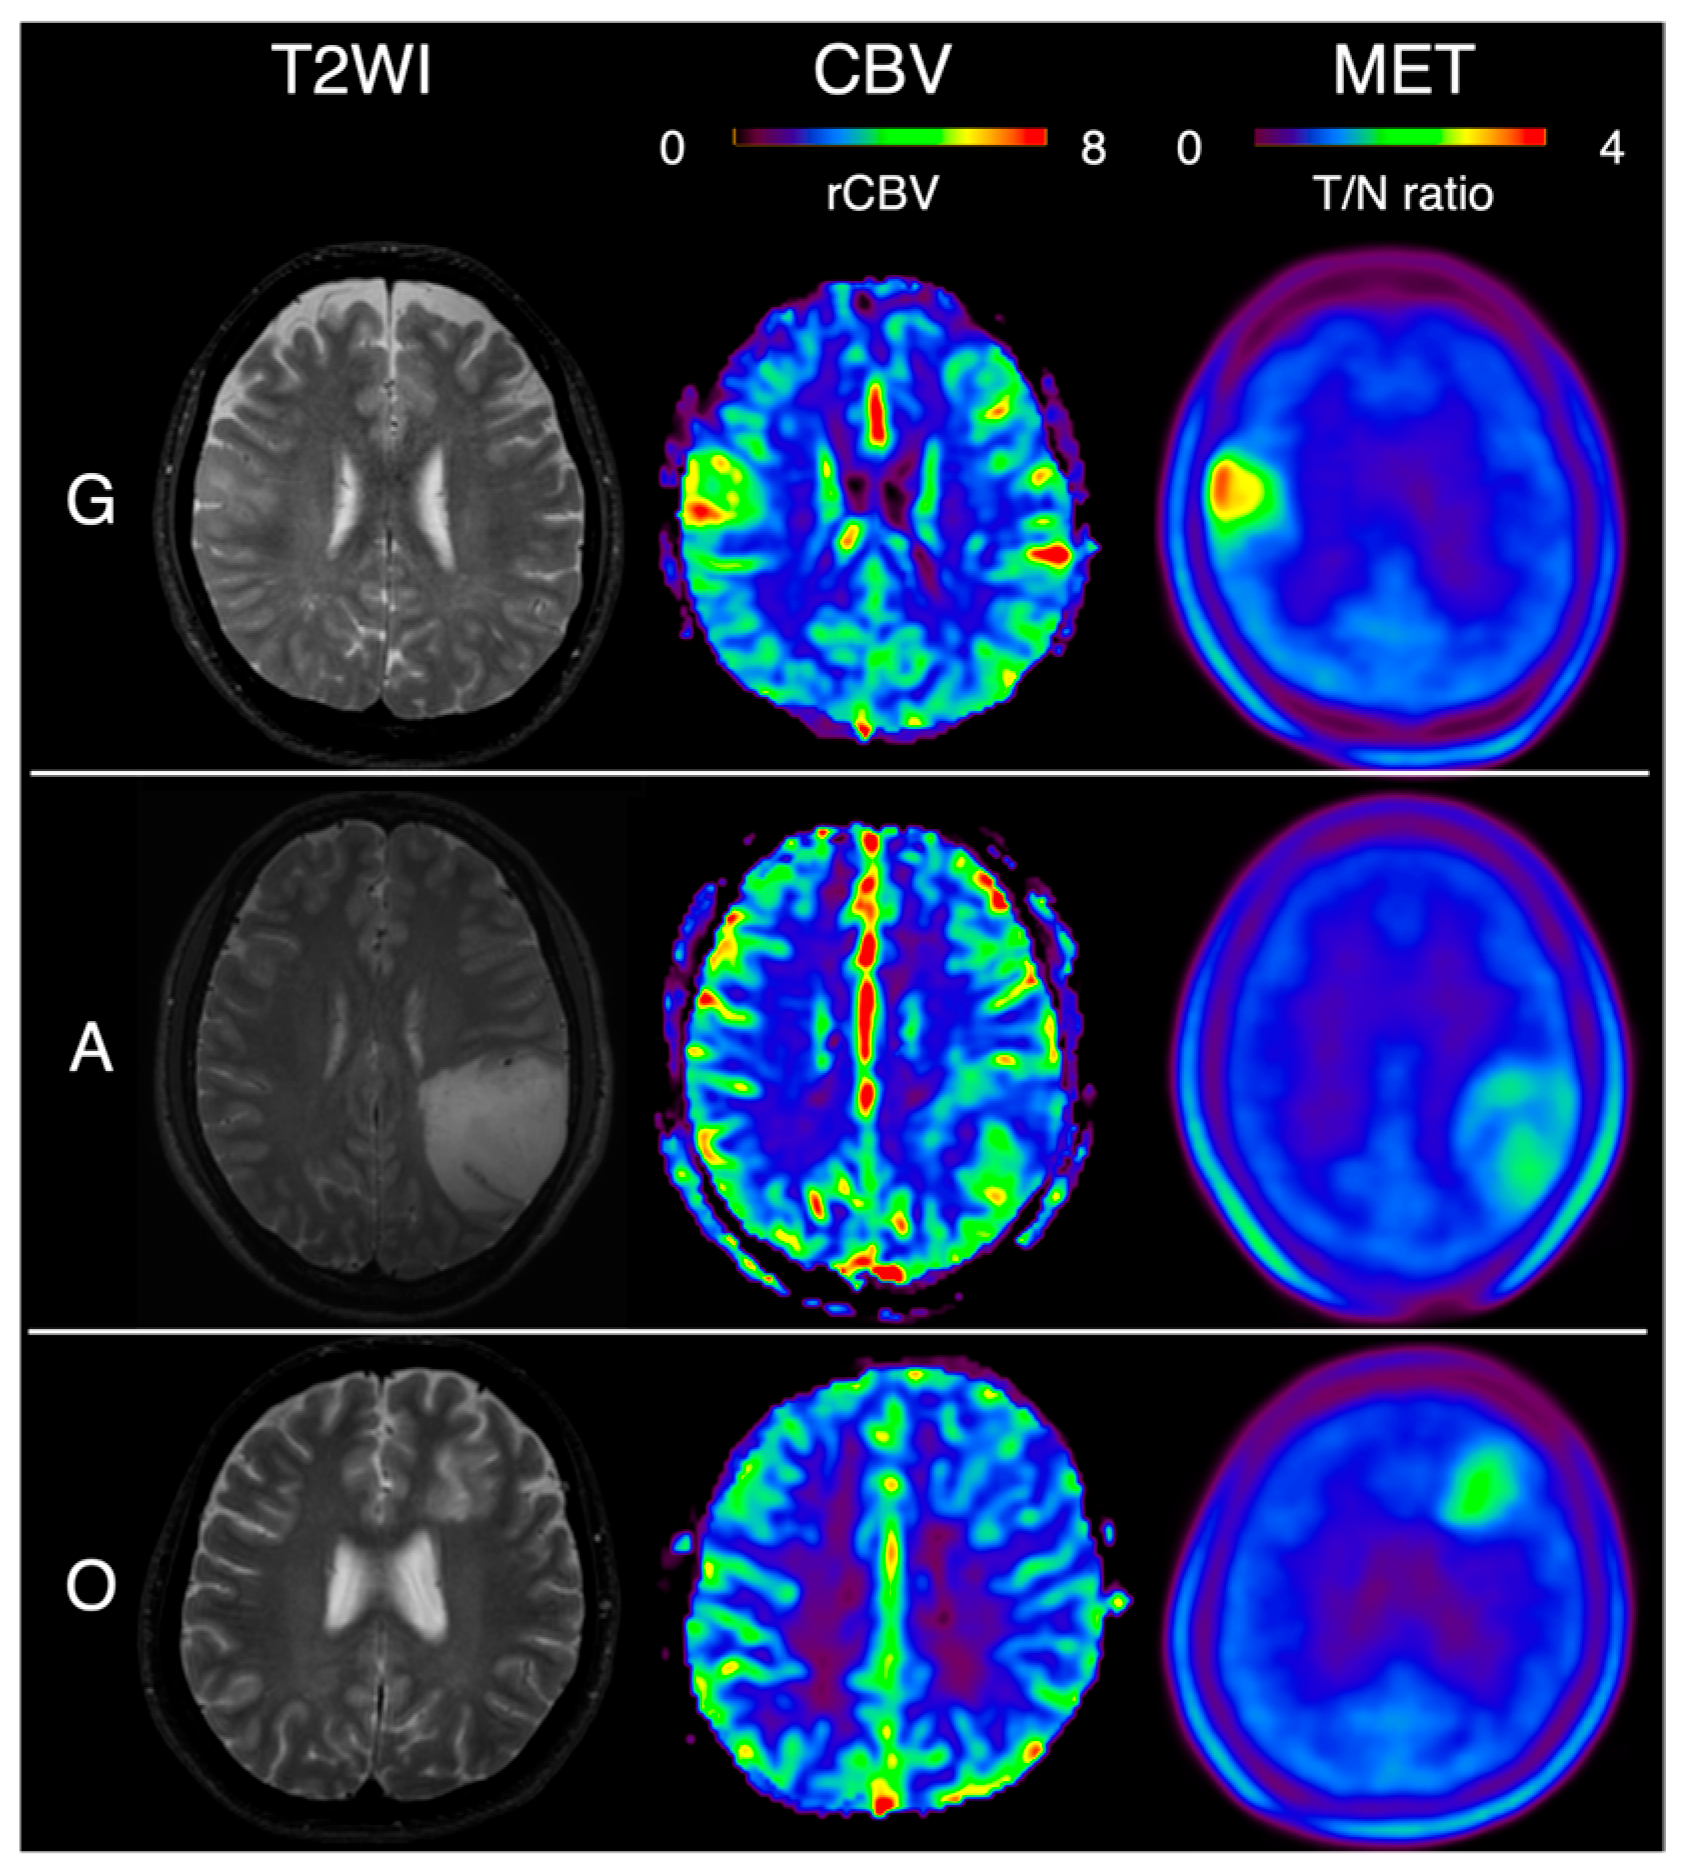

| G | glioblastoma, IDH-wildtype |

| A | astrocytoma, IDH-mutant |

| O | oligodendroglioma, IDH-mutant and 1p/19q-codeleted |